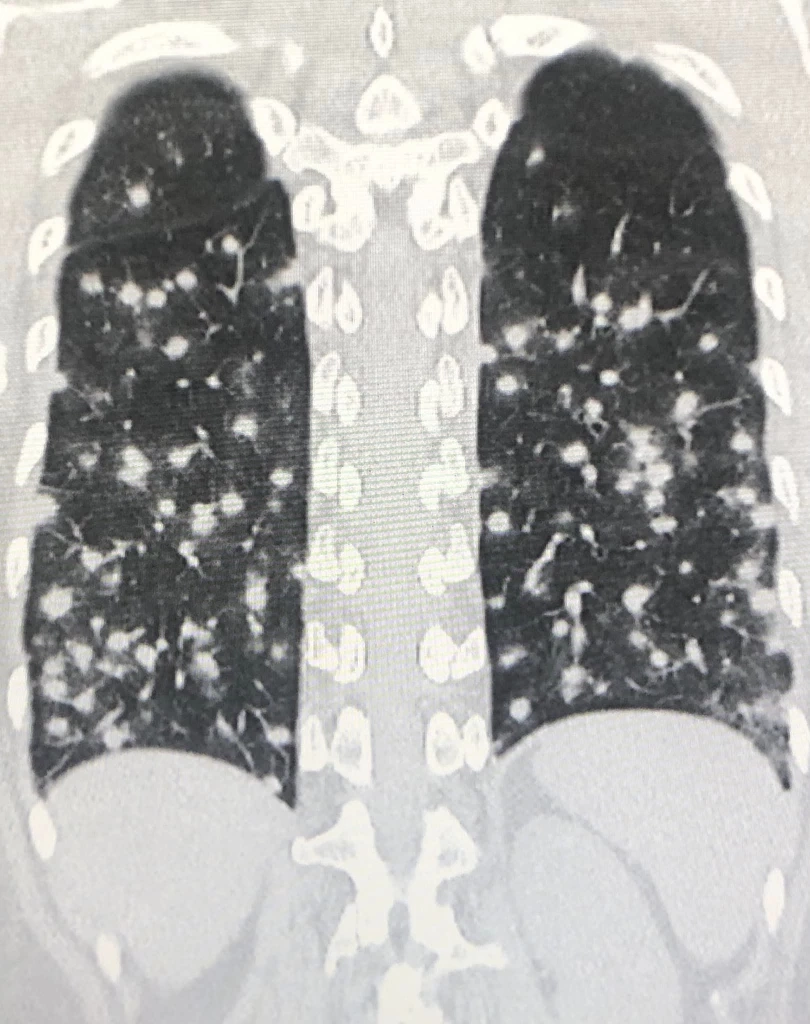

ผู้ป่วยหญิงอายุ 45 ปี ปกติแข็งแรงดี ไม่มีโรคประจำตัว วันที่ 30 กรกฎาคม 2565 ไปเที่ยวจังหวัดนครศรีธรรมราช เดินเข้าโพรงต้นไม้ใหญ่อยู่ห่างคลองวังหีบประมาณ 200 เมตร เพื่อไปดูค้างคาว ไม่ได้ใส่หน้ากากอนามัย อยู่ในโพรงต้นไม้ประมาณ 3 นาที หลังจากนั้น 15 วันเริ่มไอแห้งๆ บางครั้งไอมีเสมหะสีขาว อ่อนเพลีย ไม่มีแรง เดินขึ้นบันไดเหนื่อย เบื่อหาร น้ำหนักลด 2 กิโลกรัม ไม่มีไข้ ไม่ปวดหัว ไม่ปวดกระดูก ไปหาแพทย์วันที่ 5 ก.ย. 2565 เอกซเรย์ปอดผิดปกติ มีก้อนเล็กๆกระจายทั่วปอดทั้ง 2 ข้าง ทำคอมพิวเตอร์สแกนปอด และช่องท้อง พบก้อนเล็กๆในปอดกระจายทั่วปอดทั้งสองข้าง ก้อนในปอดด้านล่างขนาดใหญ่ถึง 1 เซนติเมตร (ดูรูป) พบก้อนในต่อมหมวกไตข้างซ้ายขนาด 0.5 x 1.1 เซนติเมตร และม้ามโตเล็กน้อย ได้ทำผ่าตัด ตัดชิ้นเนื้อจากปอดด้านซ้าย ส่งตรวจทางพยาธิวิทยา พบว่ามีเนื้อเยื่อตายและการอักเสบแบบแกรนูโลมา (necrotizing granulomatous inflammation) ไม่พบวัณโรค ย้อมสีพบเชื้อราลักษณะเป็นยีสต์ (ดูรูป) เพาะเชื้อราขึ้น Histoplasma capsulatum มีลักษณะเป็นราสาย (ดูรูป) Histoplasma อยู่ในกลุ่มรา 2 รูป (Dimorphic) อยู่ในเนื้อเยื่อมีรูปเป็นยีสต์ อยู่ในธรรมชาติมีรูปเป็นเส้นใยราสาย

สรุป: ผู้ป่วยเป็นโรคฮิสโตพลาสโมซิส จากการหายใจสปอร์ Histoplasma capsulatum หลังจากเข้าไปในโพรงต้นไม้เมื่อวันที่ 30 ก.ค. 2565 ทำให้เกิดปอดอักเสบ กระจายไปที่ต่อมหมวกไตและม้าม